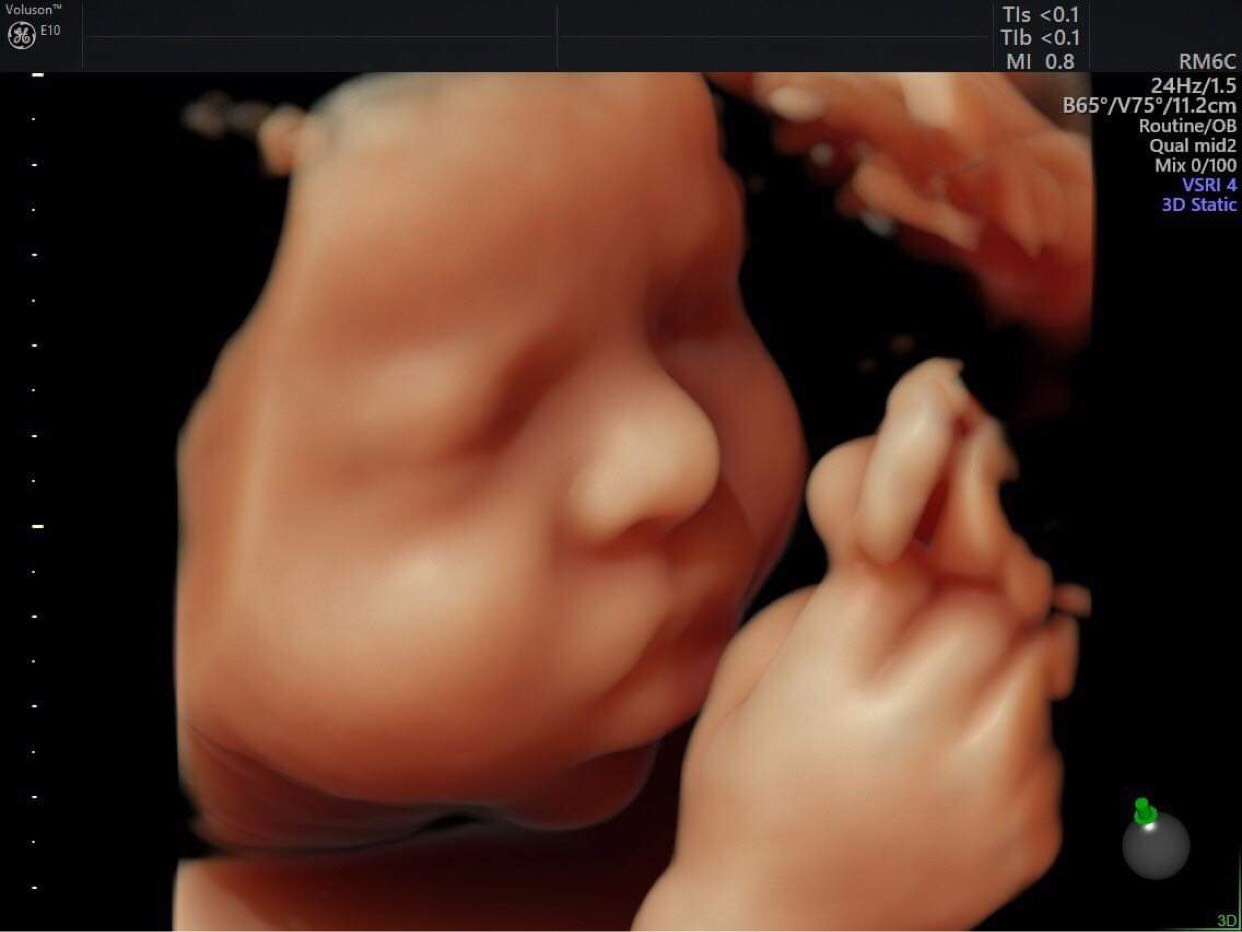

Càng về những tháng cuối thai kỳ, mẹ bầu cần thường xuyên theo dõi những dấu hiệu phát ra từ cơ thể, để theo dõi sự phát triển của thai nhi. Đồng thời cần đến cơ sở y tế theo chỉ định của bác sĩ. Vậy mẹ đã biết sự quan trọng của siêu âm thai 3 tháng cuối chưa. Theo dõi ngay nhé!

– Theo dõi và đánh giá tổng quát sự phát triển của bé trong giai đoạn cuối của thai kỳ.

– Dự kiến ngày bé yêu chào đời. Điều này giúp mẹ có thời gian chuẩn bị tâm lý tốt nhất trước khi bé chào đời.

– Xác định vị trí của nhau thai, kịp thời kiểm tra và phát hiện các dấu hiệu bất thường của ngôi thai (nếu có). Từ đó, đưa ra phương án xử lý nhanh chóng và kịp thời nhất nếu có các dấu hiệu bất thường.

– Kiểm tra số lượng nước ối của mẹ bầu tại tử cung nhằm đánh giá mức độ thích hợp của quá trình chuyển dạ.